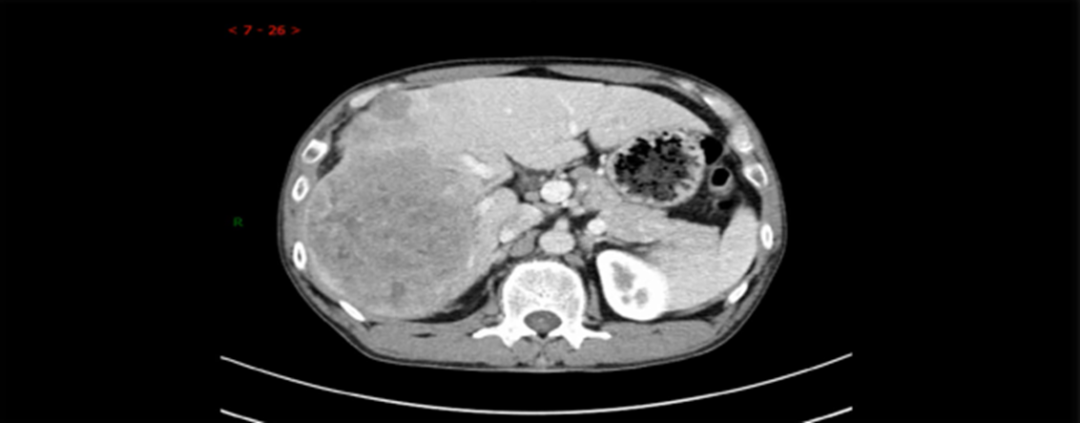

➣ 2019年4月23日,腹部增强CT:右肝巨块型肿块,大小约16*15*10cm,伴周围子灶形成;右肝静脉、门静脉右后支受侵;肿块体积 1236.63㎝³,左肝体积 863.97㎝³。

2019-4-26,TACE(雷替曲塞、多柔比星脂质体化疗+碘油、PVA/微球超选栓塞),每月1次,2019-6-14进行第二次介入,2019-7-26进行第三次介入,2019-10-14进行术后第一次介入,2020-4-15术后第二次介入。

疗效评价1

mRECIST评价标准:PR

➣ 目标病灶(动脉期增强显影)的直径总和缩小>30%

肿瘤体积明显缩小:749.25⁄1236.63 cm³ ≈60%